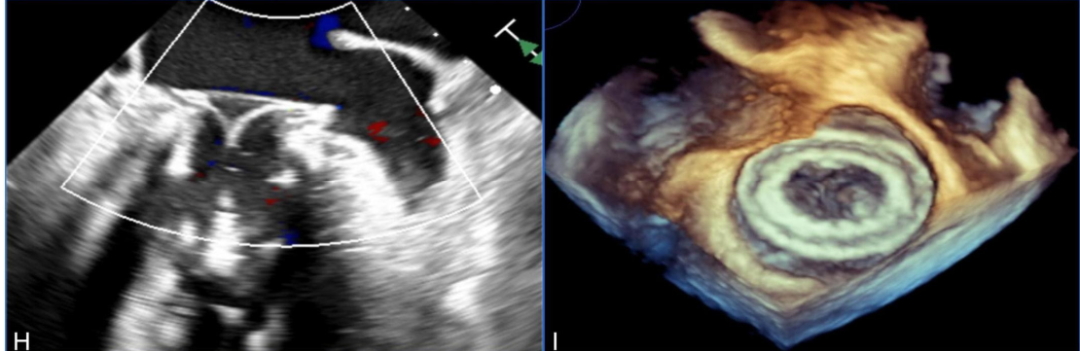

To achieve precise assessment, Professor Yang Jian’s team constructed a personalized 3D printed model of the patient based on CTA data. First, DICOM format images were imported into Materialise Mimics 21.0 software (Leuven, Belgium), where image segmentation was completed and exported as STL files. Subsequently, the STL files were post-processed using Materialise 3-Matic 14.0. Finally, the model was imported into the Polyjet 850 multi-material full-color 3D printer (Stratasys, Eden Prairie, Minnesota, USA) for printing. This printer uses materials of varying softness to accurately replicate the real texture of different structures such as the valve ring and myocardial tissue (Figure 1F–H).

Preoperatively, the model was used for bench testing, clearly observing the deployment of the released biological valve, which helped predict major complications that may occur during the perioperative period. Given that the area of the 36 mm Physio ring is 7.0 cm² and it is a D-shaped semi-rigid structure, using the conventional “valve-in-valve” technique carries a high risk of complications, thus the apical approach for implanting the Mi-thos valve system was ultimately chosen (Figure 1I).

Discussion on the Structure Literature of Xijing|3D Printing-Assisted Innovative System for Transcatheter Mitral Valve "Valve-in-Ring" Replacement SurgeryFigure 1. (F-I) Preoperative 3D printing model used for surgical planning.(F) Three-dimensional reconstruction and landing zone structure calculation based on CTA data. (G, H) Preoperative 3D printed model from the left atrial and ventricular perspectives. (I) The Mi-thos valve system adopts a D-shaped design, which fits well with the saddle-shaped mitral valve annulus.Surgical Steps